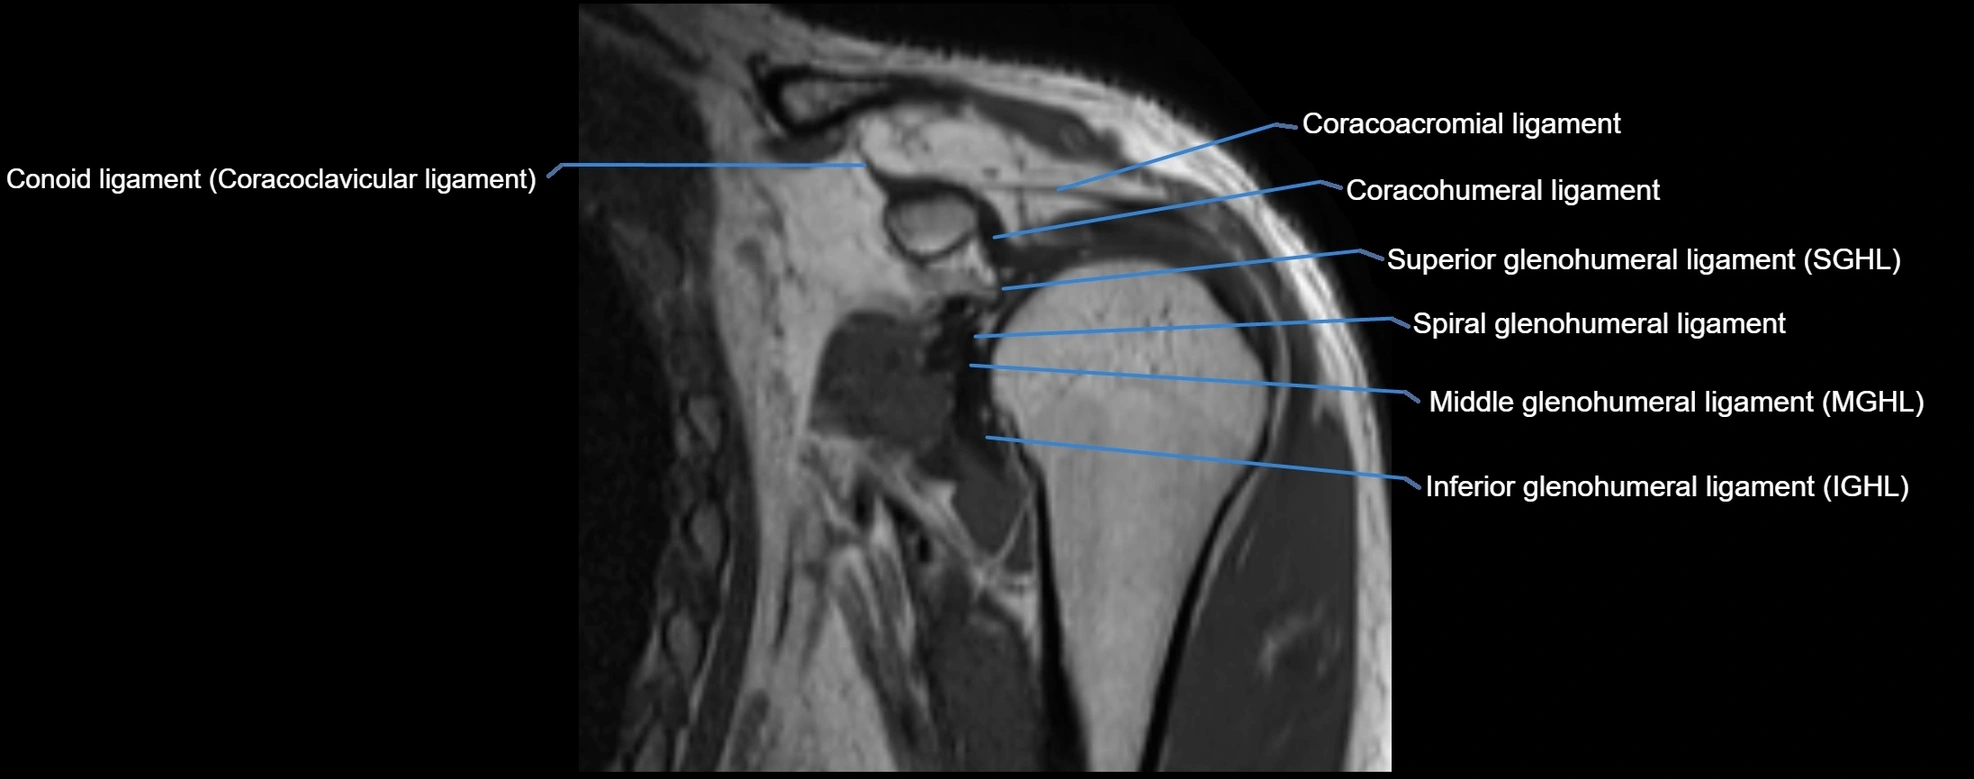

MRI Appearance

• T1-weighted images:

• Normal ligament: Low signal (dark linear band) spanning acromion to clavicle.

• Surrounding fat planes: Bright, delineating the ligament clearly.

• Marrow of clavicle and acromion: Bright due to fatty content.

• Tears: Discontinuity or irregular thickening with intermediate-to-bright signal.

• Chronic injury: Thinning, fraying, or irregular low-signal fibers with adjacent scarring.

• T2-weighted images:

• Normal ligament: Low signal, homogeneous.

• Partial tear or sprain: Focal hyperintensity or thickening.

• Complete tear: Discontinuity with fluid-bright gap between clavicle and acromion.

• Associated edema: Bright signal in distal clavicle or acromion marrow.

MRI images

image